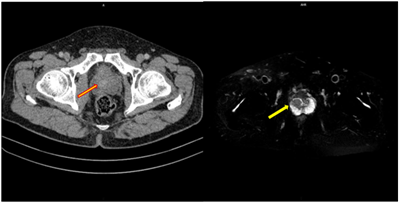

UNG THƯ BIỂU MÔ TẾ BÀO THẬN

Ung thư thận là loại ung thư thường gặp đứng thứ 14 trên toàn cầu, với hơn 430.000 ca mới được chẩn đoán vào năm 2020, và 434840 ca mắc trên toàn cầu vào năm 2022. Tỷ lệ mắc thay đổi theo khu vực địa lý, cao hơn ở châu Âu và Bắc Mỹ. Ung...